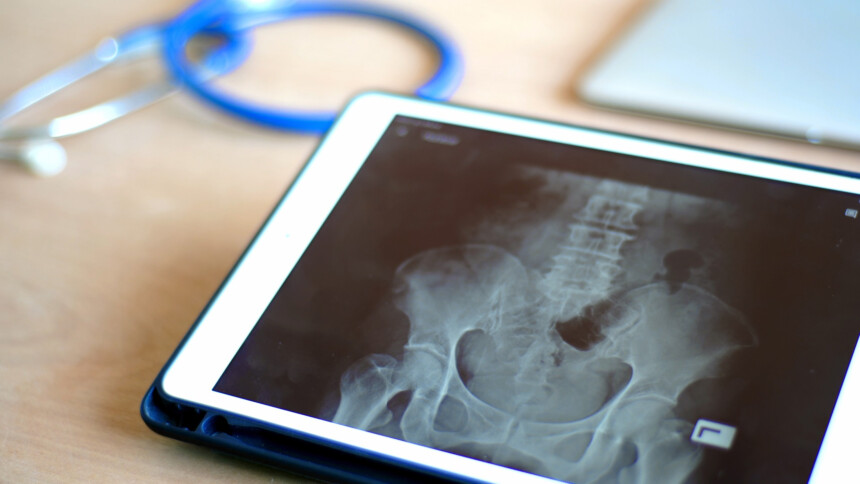

TOMOGRAFIA PELVE OU BACIA

Informações do Exame